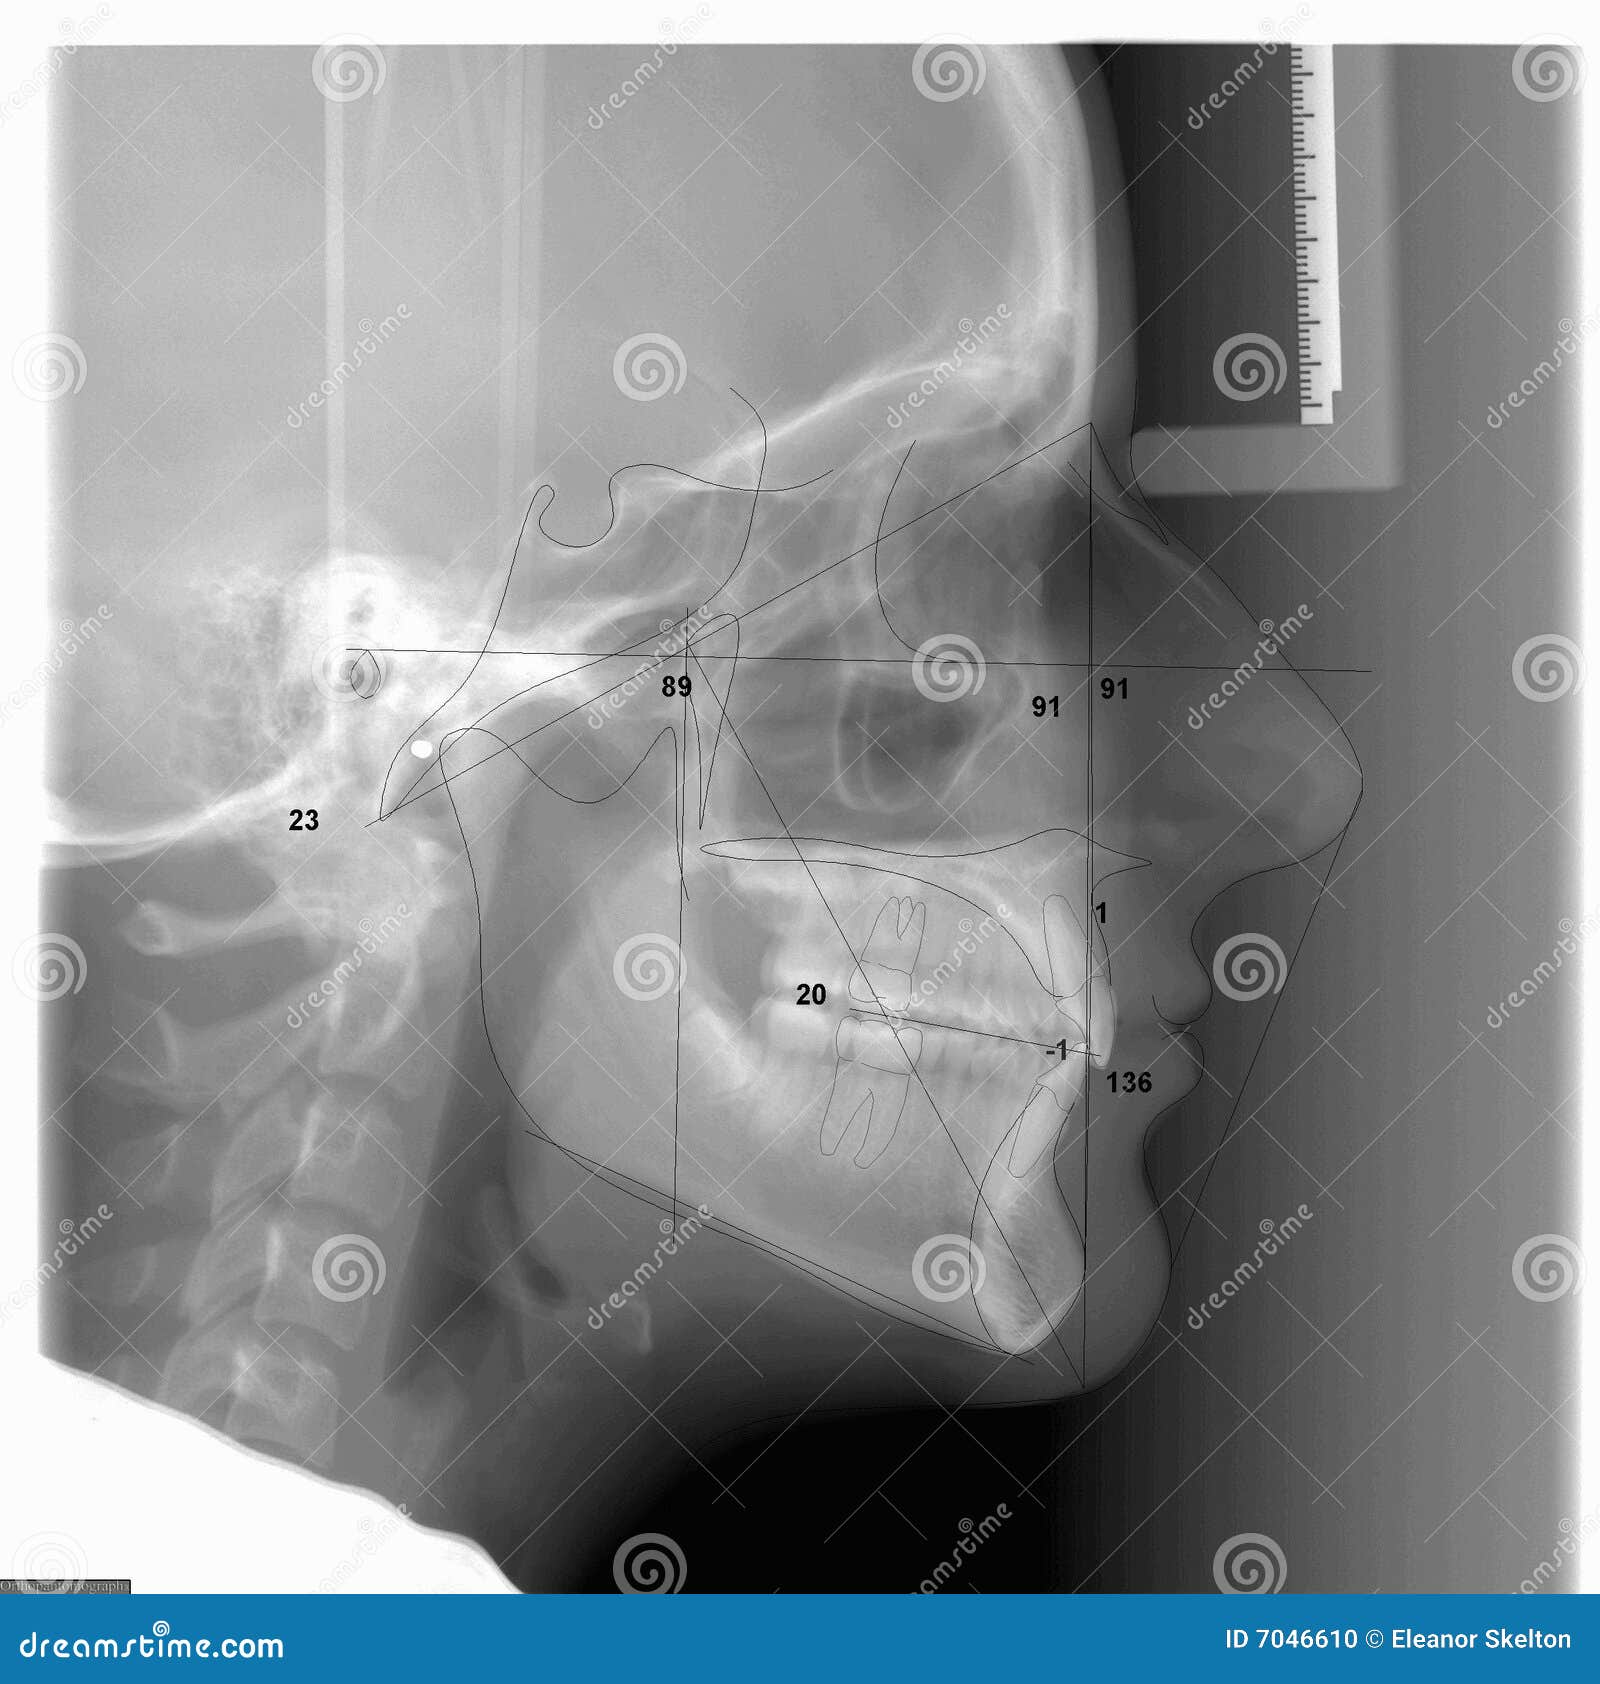

From www.dreamstime.com

A Traced Cephalometric Xray Stock Photo Image of orthodontic, ceph Cephalometric Radiograph Dental Definition a cephalometric radiograph is a radiograph of skull taken with patient’s head fixed in a cephalostat which is a device. cephalometric radiography is a standardized and reproducible form of skull radiography used extensively in. what is a ceph? this article discusses the uses, indications and basic anatomical features present on a lateral cephalometric radiograph, as well. Cephalometric Radiograph Dental Definition.